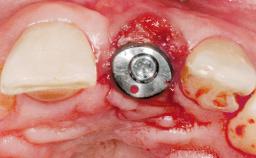

Immediate Flapless Placement of an Implant in a Maxillary Right Lateral Incisor Site

This 43-year-old male patient, a non-smoker, came to our practice because of a fracture of tooth 12 caused by a bicycle accident. Due to the combined para- and infrabony crown and root fracture, tooth extraction, and subsequent implant placement were suggested to the patient as the therapy of choice. The patient had high esthetic expectations with regard to the treatment outcome and asked for an immediate fixed provisional restoration. His individual esthetic risk profile summed up to a medium esthetic risk.

Placement Protocol Immediate implant placement

Tooth Site Maxillary incisor or canine

Socket Morphology Single-root socket

Socket Integrity Sufficient, with intact bone walls

Bone Volume Sufficient, with intact walls

Loading Protocol Immediate

Retention Screw-retained Screw-retained